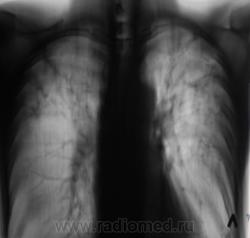

Диссеминированный ТБС, фаза инфильтрации... и хронический бронхит.

То. что ТБС - сомнений не вызывает. А вот какой - пусть разбираются фтизиатры, главное больного отправить по правильному направлению. Там и каверны и диссеминация...

ПОХОЖЕ НА  2-Х СТОРОННИЙ  СПЕЦИФИЧЕСКИЙ  ПРОЦЕСС.

С  2-Х СТОРОН   В  ВЕРХНИХ ОТДЕЛАХ  НА  ФОНЕ  ПНЕВМОФИБРОЗА МНОЖЕСТВЕННЫЕ

ОЧАГОВЫЕ ТЕНИ. ХОРОШО  БЫ  ВЗГЛЯНУТЬ НА  РЕНТГЕН- АРХИВ.

Выражен пневмофиброз в верхних и средних отделах легких, с наличием очаговоподобных теней преймущественно средней плотности. Нижние поля эмфизематозные. Корни структурные, содержат мелкие кальцинаты лимфоузлов ( не люблю выражение "фиброзно изменены"). Cor вертикального положения. Неплохо-бы узнать профмаршрут больного. В диф. ряд должны быть включены фиброзирующие процессы легких (основные-альвеолит, пневмокониоз, ТБС). Показано УЗИ щитовидной железы.

Вот такой случай. Пациент на учете по поводу фиброзно-кавернозного туберкулёза.

Сомнения вызвала тень, помеченная желтой стрелкой. На наш взгляд, это был растущий гриб. Однако возобладало мнение, что "это" участок некроза, так как не было "симптома погремушки"